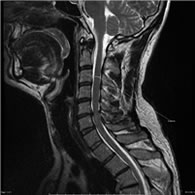

El canal estrecho cervical consiste en la reducción del diámetro anteroposterior del canal espinal en la región cervical. Es producto de un proceso degenerativo relacionado con el envejecimiento. Es la causa más frecuente de compromiso medular cervical de origen no traumático en pacientes de más de 60 años.

• Resonancia Magnética de la columna vertebral es el principal método de estudio para el canal estrecho cervical. Permite ver la compresión medular y los niveles en los que ocurre; permite evaluar si hay señal de sufrimiento medular y si la compresión es predominantemente anterior o posterior.